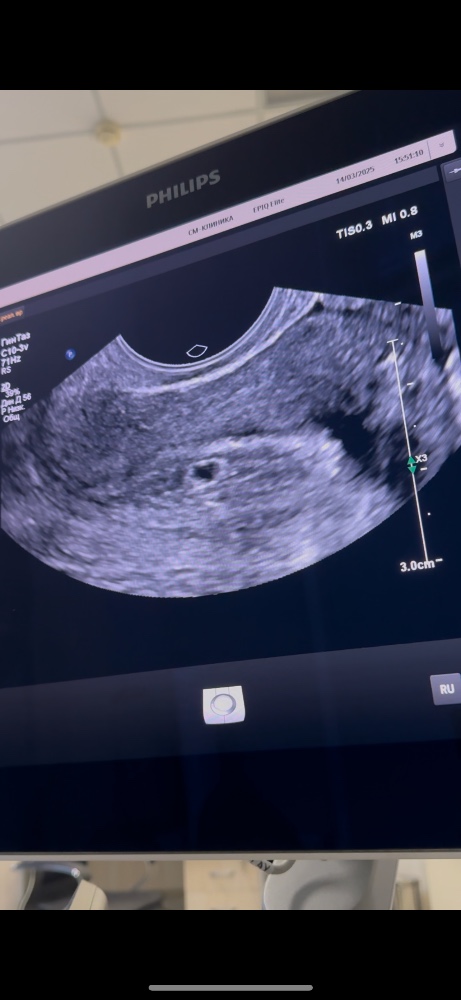

Моё лечениеВчера пришел анализ хгч - 1,220, сходила на узи, моя врач заметила небольшую гематомку, сказала что именно она и кровит, сказала что ничего страшного, она либо выйдет сама либо рассосется, естественно принимаю для этого нужные лекарства.

Малышок на месте и даже немного вырос :) У нас с мужем вчера было полное замешательство, тк мы шли на узи с уверенностью что нам скажут что все отслаивается и скоро начнутся месячные.

Вы заметили, малыш сердечком)))))